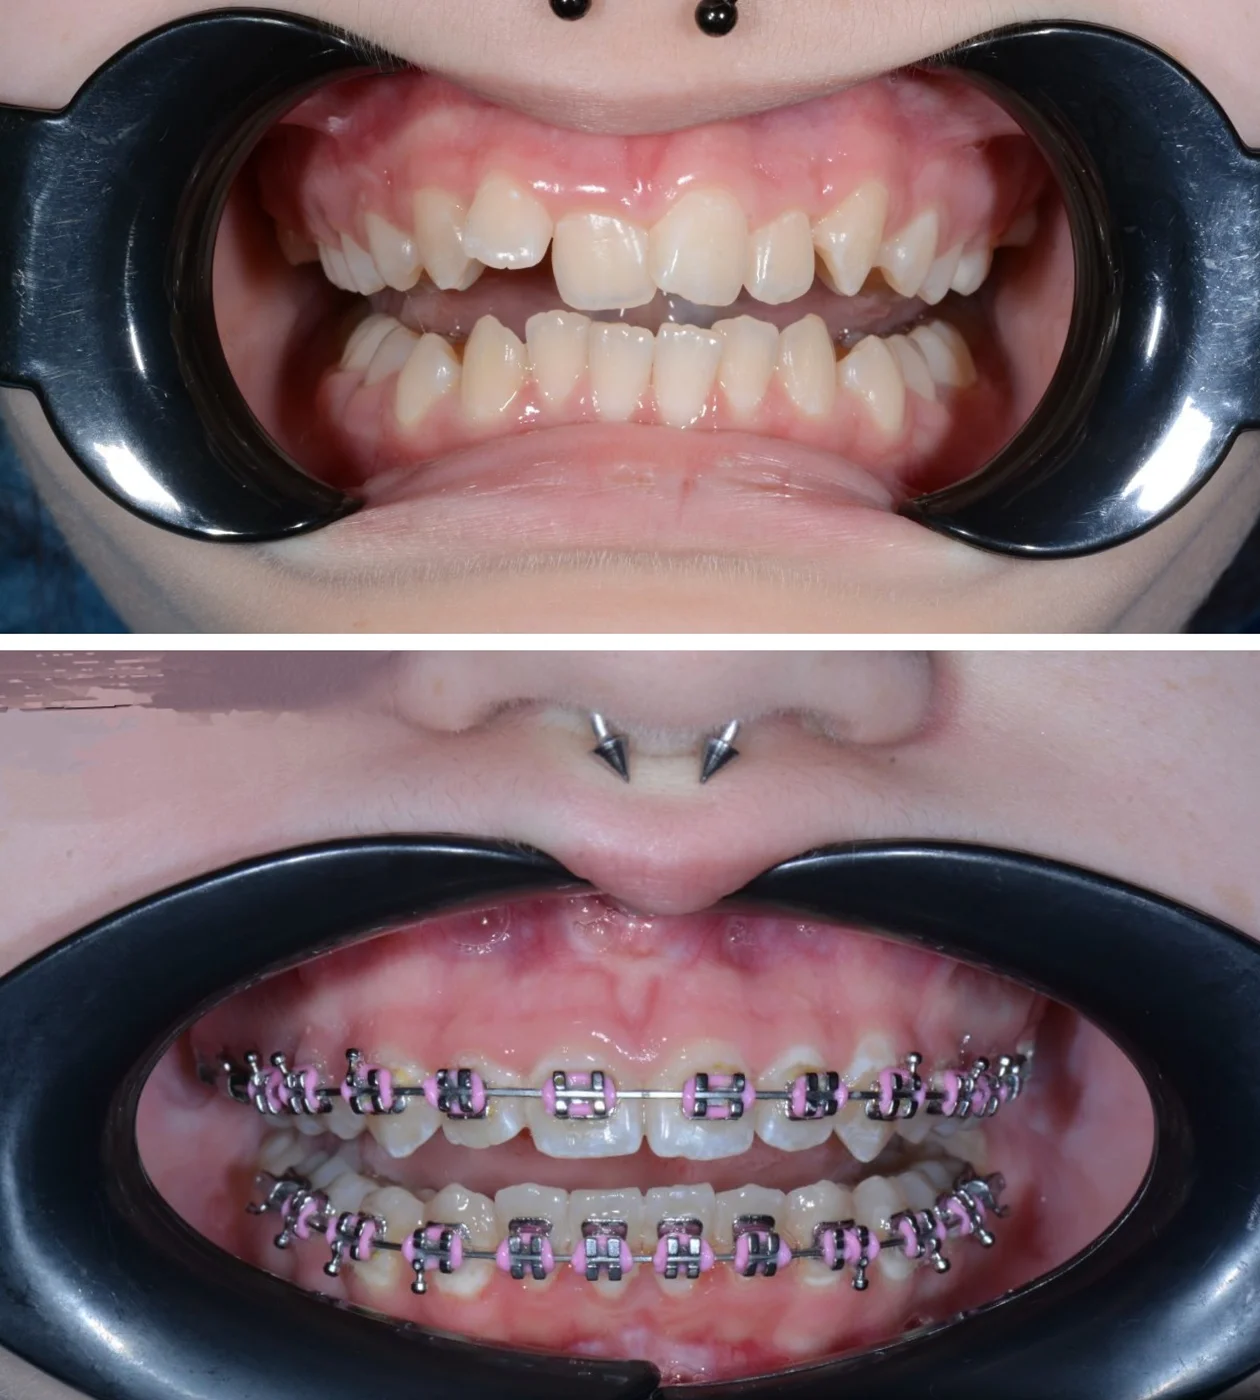

Лікування патологій прикусу

Корекція прикусу за допомогою брекет-систем, елайнерів та мікроімплантів — для здорової та естетичної посмішки.

ортодонтичних лікувань з брекет-системами

390+